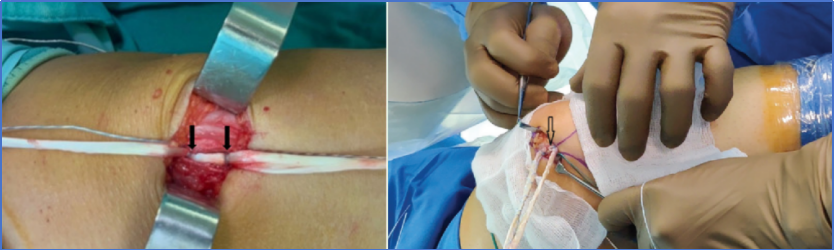

①在大腿上绑扎止血带。进行诊断性关节镜检查,以清除髌骨或股骨外侧髁上任何松动的骨软骨体。处理其他关节内病变,并评估髌骨轨迹[图1]。

图1:一名27岁男性,其左膝关节出现复发性髌骨脱位。计划对他实施髌股内侧韧带重建术。在进行术区皮肤消毒和铺单后,标记出了相关解剖标志。箭头所指分别为舍特勒点、髌骨上内侧缘以及用于获取股薄肌移植物的纵向切口。